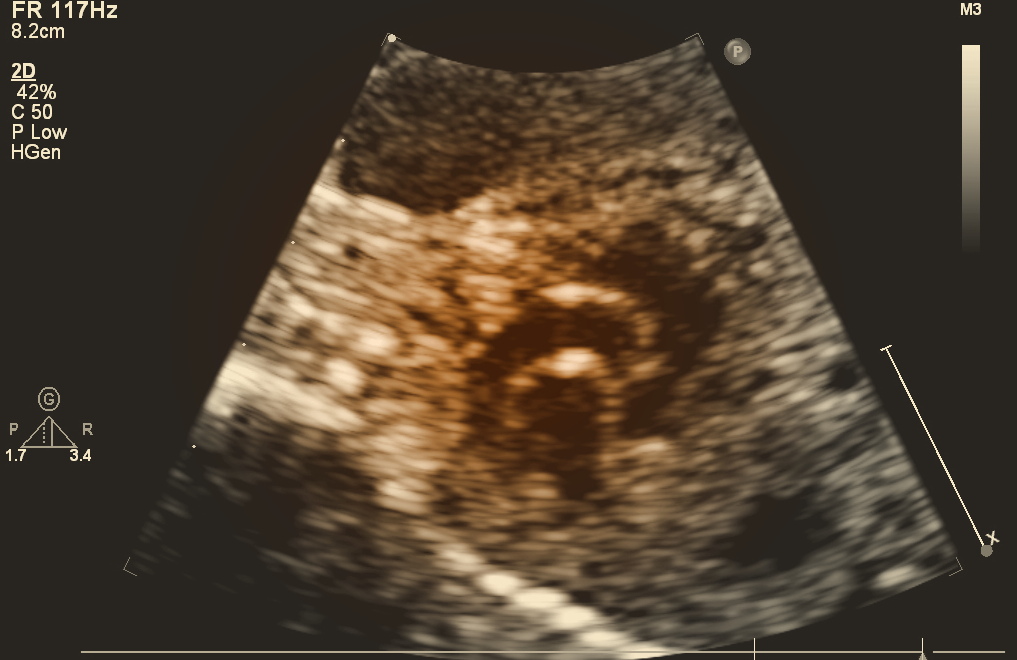

Fetal echocardiography is a non-invasive diagnostic imaging technique that employs ultrasound to visualize and evaluate the developing heart of a fetus. Fetal echocardiography is a critical tool that allows medical professionals to assess the fetal heart and identify potential abnormalities at an early stage.